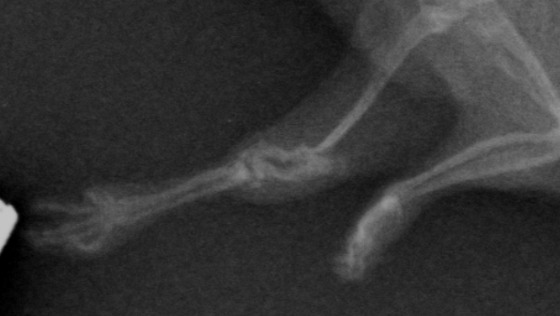

Jeśli trudno jest Wam ocenić po filmiku, przedstawiam zdjęcia rentgenowskie:

Opis RTG w opisie badania od weterynarza: "znaczne skrócenie kośćca oraz dystalne oddzielenie od stawu. Ubytek kości ramiennej."